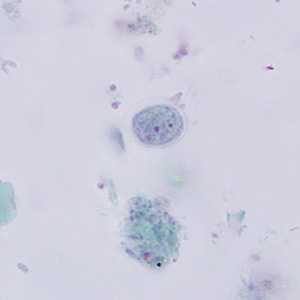

I. buetschlii cysts stained with trichrome.

Figure A: Cyst of I. buetschlii stained with trichrome. In this specimen, both the nucleus and large glycogen vacuole are visible.

Figure B: Cyst of I. buetschlii stained with trichrome. In this specimen, both the nucleus and large glycogen vacuole are visible.

Figure C: Cyst of I. buetschlii stained with trichrome. In this specimen, both the nucleus and large glycogen vacuole are visible (arrow).

Figure D: Cyst of I. buetschlii stained with trichrome. In this specimen, both the nucleus and large glycogen vacuole are visible.